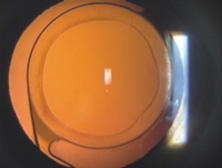

Because of these compounding developments, David Apple began his important work with Randy Olson and in 1983 founded the Center for Intraocular Lens Research at the University of Utah. They were a uniquely qualified combination. Dr. Apple was board certified as both a pathologist and ophthalmologist; Dr. Olson was an academic ophthalmic surgeon. Much like Harold Ridley and Peter Choyce, they began their dedicated quest to improve the condition of pseudophakia. They solicited autopsy specimens and wrote innumerable articles about IOL design, centration, and complex IOL–ocular interactions. One of their most important articles, published in 1985, was a position article citing the advantages of capsular bag placement and recommending it over ciliary sulcus placement, still a controversial issue at the time.44 The eyes submitted to them that year demonstrated capsular bag fixation in 31%, ciliary sulcus fixation in 11%, and asymmetric bag–sulcus fixation in 58%.45 At that time, 85% of surgeons still preferred planned ECCE as their surgical technique.46 While in Utah, Apple and Olson saw the problems created by ARTs solved with the invention of capsulorrhexis, almost simultaneously reported in 1986 by four surgeons from around the world. Two presented articles at the Welch Cataract Congress in Houston that year, and two reported their techniques independently. The discovering surgeons in alphabetical order are Drs. Calvin Fercho (Welsh Cataract Congress, Houston, 1986), Howard Gimbel (video presentation at the annual meeting of the ASCRS in Boston, 1985),47 John Graether (Welch Cataract Congress, Houston, 1986),48 and Thomas Neuhann (video presentation at the meeting of the German Ophthalmological Society in Heidelberg, 1985).47 With this technique, and the creation of an approximate diameter of 5 mm, symmetric placement of any IOL could be guaranteed. It still took several years for the majority of ophthalmologists to incorporate continuous curvilinear capsulorrhexis (CCC) into their surgical routines. In 1988 Dr. Apple relocated the laboratory to the Storm Eye Institute at the Medical University of South Carolina in Charleston. Reflecting new challenges, his laboratory name would be changed to the Center for Research on Ocular Therapeutics and Biodevices. From there, he and his staff, residents, and research fellows continued to receive autopsy specimens from around the world and eventually demonstrated, in the largest autopsy specimen study to date, a decline in asymmetric placement to only 10% of eyes with foldable lenses submitted in 1998.45 Early in his work there, Dr. Apple recruited Dr. Kensaku Miyake's retrociliary photographic analysis method to locate and analyze IOL placement within the eye (Fig. 18). With increasing video sophistication and use of the process by Dr. Apple and his colleagues, Dr. Miyake himself generously expanded the name of the procedure to be called the Miyake-Apple technique. After cancer was diagnosed in Dr. Apple and he was successfully treated, the center was relocated to Salt Lake City in 2002, where it has been permanently designated as the David J. Apple, MD, Laboratories for Ophthalmic Devices Research. In the days when the laboratory was in Charleston, Dr. Apple worked with industry representatives and surgeons to refine IOL design to ensure that capsular bag residence would be as consistent as possible, thereby reducing lens contact with other eye structures in both routine and complicated situations (Figs. 19 and 20). J.A.D. had the great pleasure of working with him in his laboratory to help improve an already sophisticated haptic configuration in a one-piece all-PMMA IOL. At that time, we thought that the entire haptic should be C-shaped so that even its distal end could be recruited for capsular equatorial support (Fig. 21). We studied resistance to haptic compression, attempting to make it softer and more uniform through diameter reductions from 13.0 to 11.5 mm 2.5 mm (Fig. 22). These efforts contributed to the development of the Pharmacia model 811, which, along with others of its day, may have represented the height of single-piece PMMA IOL development (Fig. 23).49